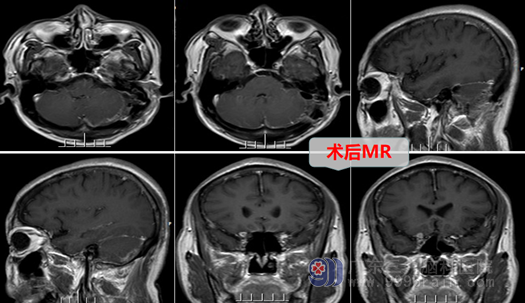

外十科团队对何大叔制定了严密的手术方案:双镜(显微镜及神经内镜)结合及神经电生理监测下前庭神经鞘瘤切除术。主管医生向何大叔及其家属讲解病情后取得了手术同意,手术当日由外十科主任欧阳辉教授主刀,在全麻下为何大叔进行精细的左侧桥小脑角占位性病变切除术,整个手术过程顺利,肿瘤被全部切除,患者的面神经、耳蜗神经都保存良好,后组颅神经、三叉神经、脑干等也未受到任何损伤,术后的何大叔恢复良好:没有面瘫,没有出现吞咽困难等。